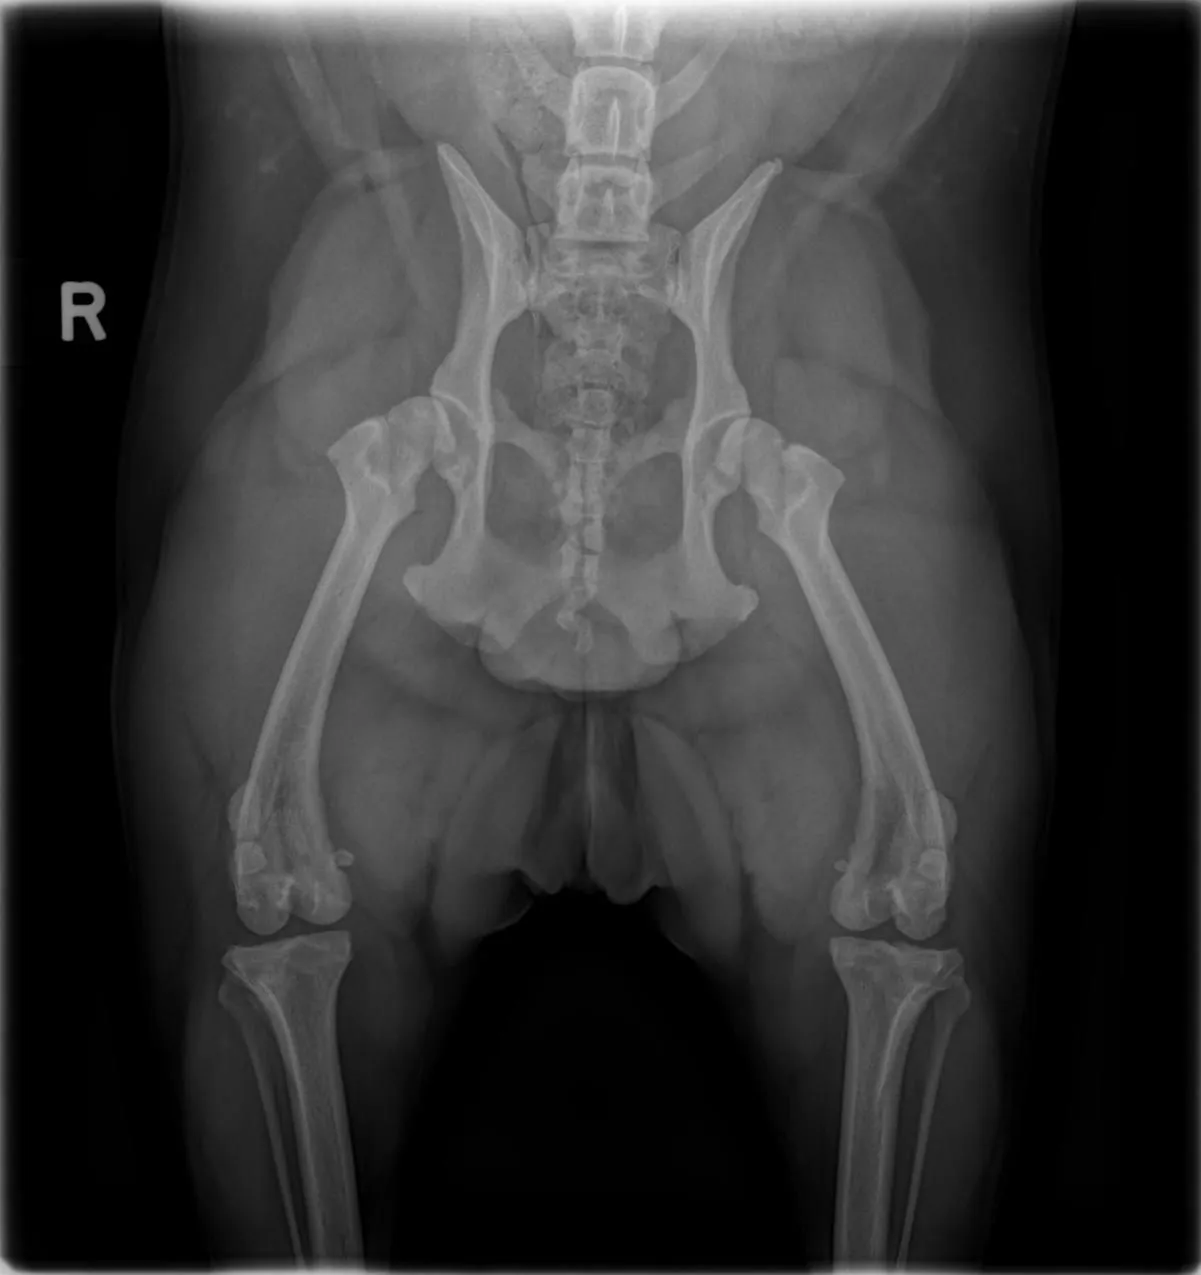

Thanks again to all for the help. Still waiting to hear what the orthopedic surgeon has to say about the x-rays that were done. Trying to keep her from running too much right now and it is becoming challenging to do so. Each night she looks at me like "Are we going to play fetch?".

Here are the x-rays that i received from the vet. Not sure if anyone on here can look at them and see what is going on.